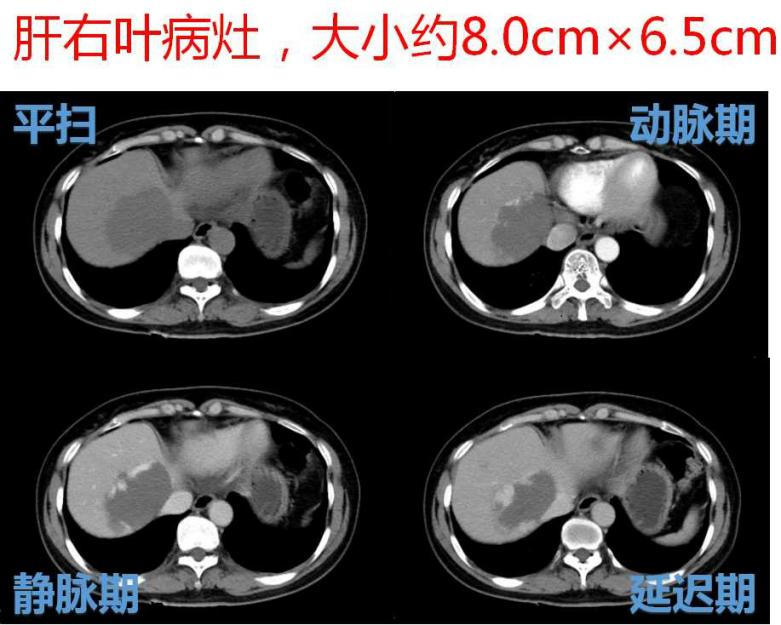

日前, 微创介入科为一名肝内多发大血管瘤患者实施肝动脉介入栓塞术,轻松解决了患者的疾病所带来的痛苦和精神压力,术后患者腹痛及腹胀等症状基本缓解,生活质量得到了明显提高。此项技术安全有效。该患者为一名中年女性,因上腹部隐痛伴腹胀行腹部CT检查,发现肝内多发血管瘤,其中最大2处病灶大小分别为8.0cm×6.5cm、7.0cm×5.6cm。

DSA造影示:肝左、右动脉明显增粗,肝左、右叶可见多发充填式片状及结节状爆米花样强化血管湖,呈弥漫性分布。静脉期门静脉主干显影尚可。

分别将微导管超选至肝左、右动脉血管瘤供血动脉,再将超液态碘化油10ml与平阳霉素16mg充分混匀后行瘤供血动脉栓塞。

栓塞后行DSA示:肝内血管湖染色基本消失,碘油在血管瘤内聚积良好。术程顺利,术中术后患者均无明显不适。